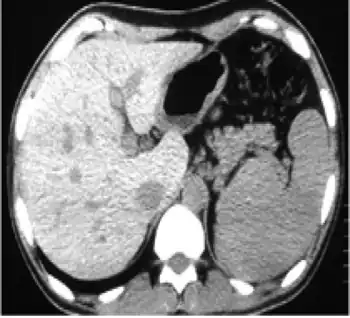

In non-contrast abdominal computed tomography, increased density of liver compared with spleen was reported

Imaging

MRI may be utilized in order to assess the extent to which iron has been deposited in certain tissues and organs, however does not have significant weight in the diagnosis of the condition.[5]